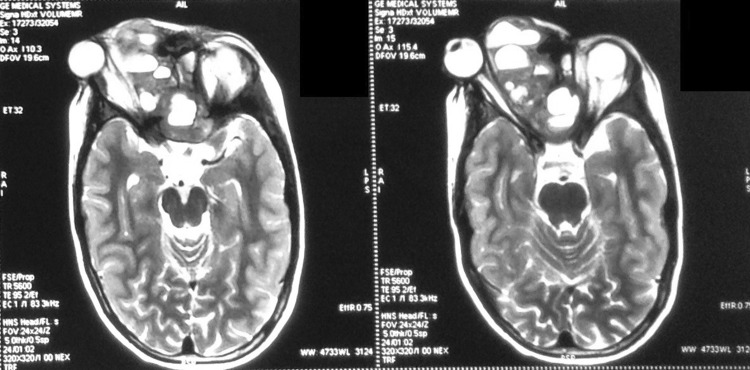

Fig. 1.

Case 2—coronal T2W MRI sequences on Initial presentation